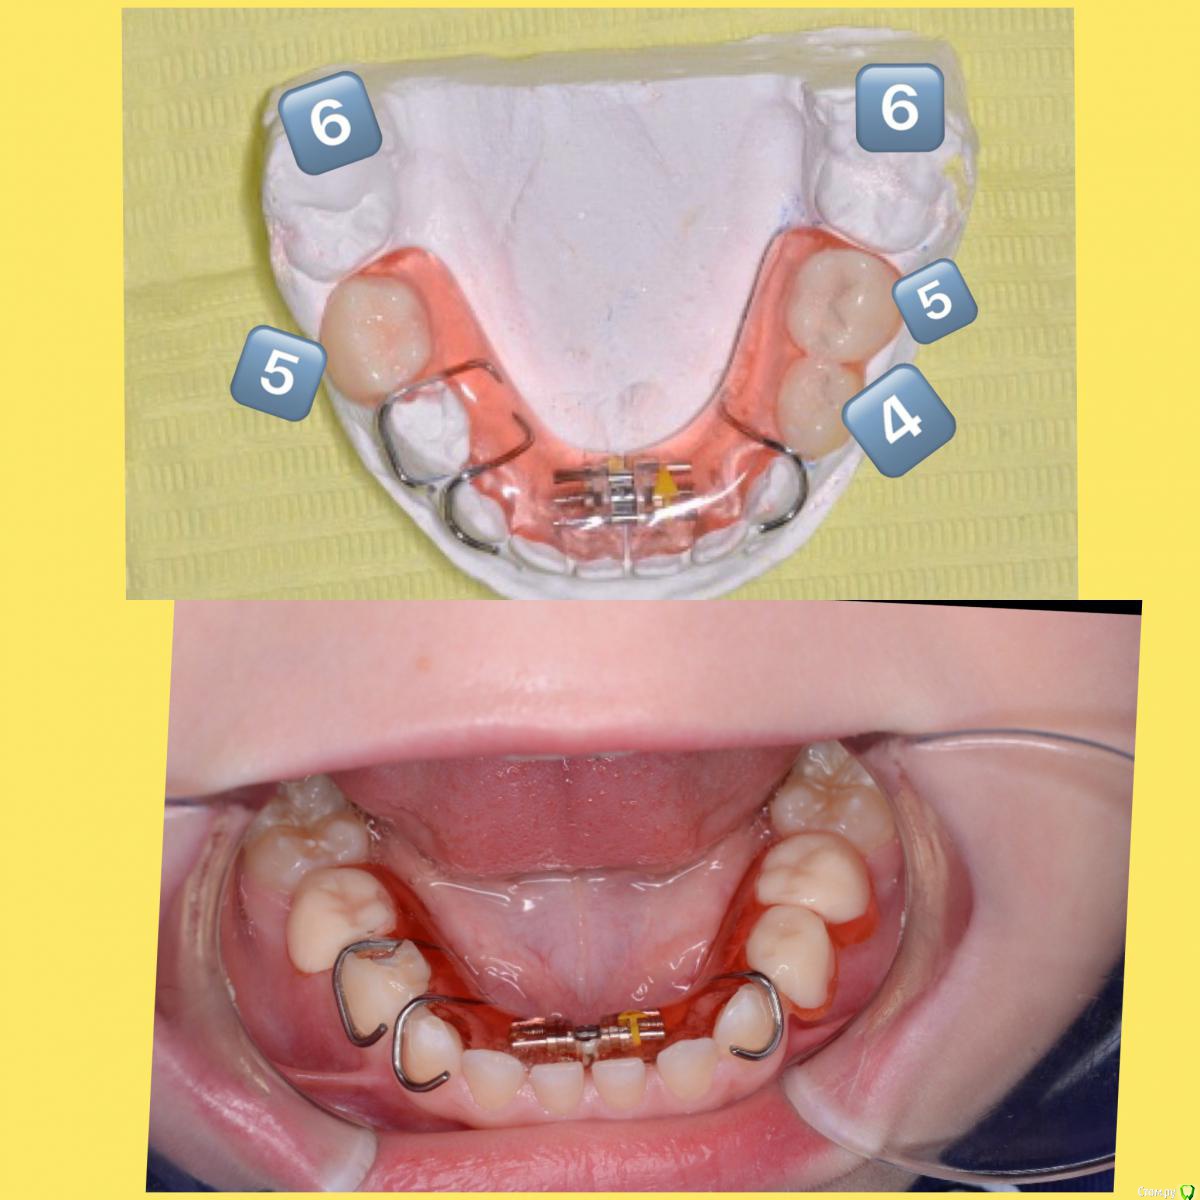

CRAZYDUCK Опубликовано 7 мая, 2018 Автор Поделиться Опубликовано 7 мая, 2018 Немного о фиксаторах места после преждевременной потери временных моляров . Каждый случай индивидуален , выбор конструкции порой сложен и на мой взгляд роль родителей в адаптации ребёнка к фиксатору места очень важна . В случае преждевременной потери 5 временных ( вторые временные моляры) фиксация места нужна всегда ! Если 6 зубы ещё не прорезались , то объясняем родителям стратегическую важность регулярных осмотров , периодичность осмотров зависит от предполагаемого времени прорезывания 6 зуба . Если 6 зубы уже есть в полости рта , то сразу изготавливаем фиксатор места ( несъёмный в приоритете ).Если же потеряли 4 временные ( первые молочные моляры), то большая вероятность , что медиального смещения 6 и 5 временного не произойдёт ( из своего опыта могу сказать , что случаи с выраженным дефицитом места - исключение). В том случае , если 4 временный потеряли , а 6 постоянный ещё не показался , то я выбираю тактику наблюдения каждый месяц ( опять же , если нет выраженного дефицита места ). 3 Ссылка на комментарий

CRAZYDUCK Опубликовано 7 мая, 2018 Автор Поделиться Опубликовано 7 мая, 2018 И вариант несъёмного фиксатора , здесь видно , что 6 зуб уже хорошо так вперёд проехался . Но не забываем , что ширина временных 5 зубов больше ширины постоянных 5 зубов примерно на 2-2,5 мм. 4 Ссылка на комментарий